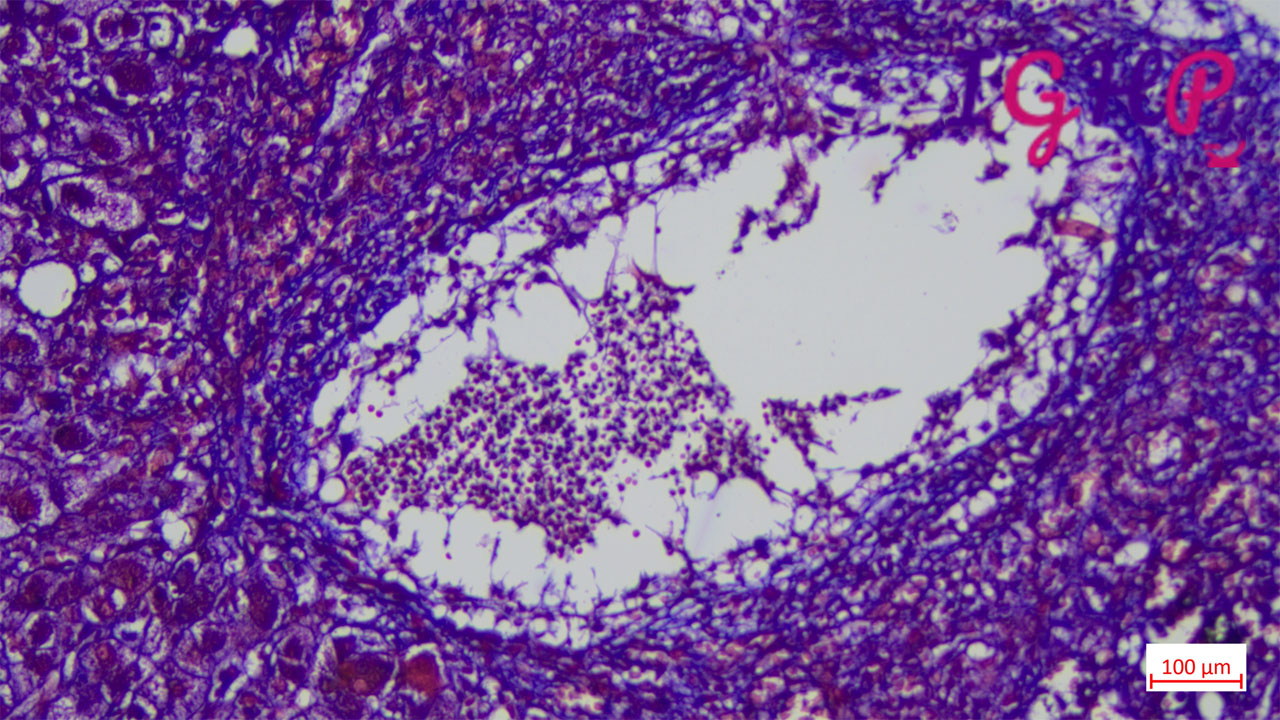

Microscopic Images-

Microscopic examination showed an areas of perivenular hepatocyte loss with prominent central perivenulitis.

Special Stains Performed-

MT and Rhodanine stains performed no increase in fibrosis or copper stores.